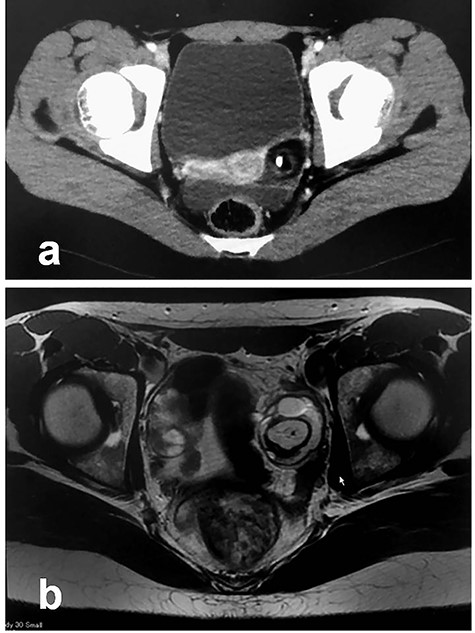

Patient 3: In a 13-year-old girl with abdominal pain, plain CT revealed bilateral ovarian tumors (Fig. 5a: left tumor and Fig. 5b: right tumor). Further examination, including MRI, revealed bilateral ovarian MCTs (Fig. 5c: left tumor; 77 cm × 70 cm, Fig. 5d: right tumor; 115 cm × 90 cm). During laparoscopic surgery, torsion of the left ovarian tumor was released, and each mass was placed in a specimen retrieval bag and removed (left tumor, Fig. 6a–d; right tumor, Fig. 6e–h). Both tumors were large, and content spillage was recognized during surgery. Peritoneal lavage was performed using large amounts of warmed fluid. Pathologic examination of both tumors confirmed the diagnosis of bilateral MCTs. The patient has been doing well without evidence of recurrence. She subsequently established a regular menstrual cycle.

Radiologic findings in Patient 3; (a): Plain CT showing the left-sided tumor (white arrow); (b): Plain CT showing the right-sided tumor (white arrow); (c): MRI showing the left-sided tumor (white arrow); (d): MRI showing the right-sided tumor (white arrow).